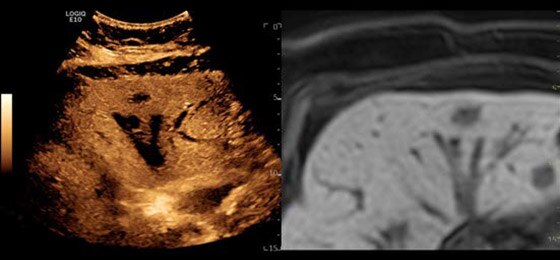

Neonatal Spine, L8-18i-D